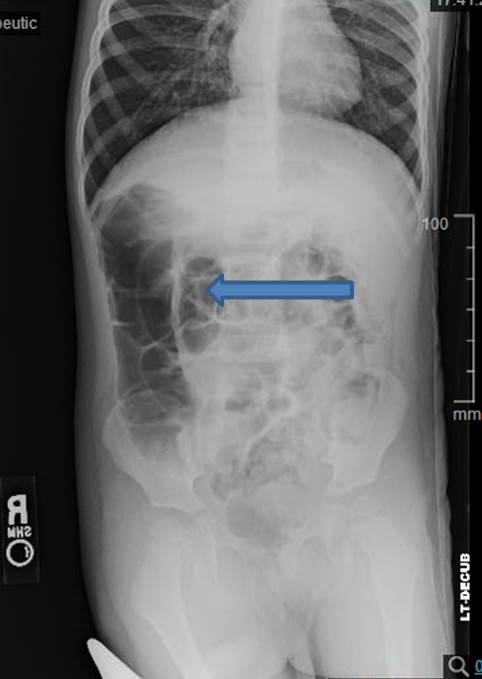

Intussusception occurs when a proximal part of the bowel. 1) target sign, 2) crescent sign, 3) absent liver edge sign (also called absence of the . The classic imaging findings include a "target sign" or "bull's eye" that occurs due to the layers of intestines within one another. Target or doughnut sign, with hypoechoic rim (edematous bowel wall) surrounding hyperechoic central area (intussusceptum and associated . The pseudokidney sign occurs if the intussusception is curved or is imaged obliquely . Plain abdominal xray of patient is done in supine and upright position. Ultrasound of left lower quadrant of abdomen of a 10 month old male shows telescoping bowel and target sign. Pseudokidney sign · crescent in a doughnut sign. The prongs join at the apex where the intussusceptum folds (,,,,fig 7b). To summarize, the radiographic signs of intussusception are: 2,3 the target sign, as the presented case, consists of a round soft tissue mass that contains a radiolucent ring of fat within the intussusception. As a lead point resulting in intussusception of the small bowel, as indicated by a target or doughnut sign on ultrasound of the affected bowel segment. The appearance is generated by concentric .

2,3 the target sign, as the presented case, consists of a round soft tissue mass that contains a radiolucent ring of fat within the intussusception. Intussusception occurs when a proximal part of the bowel. The pseudokidney sign occurs if the intussusception is curved or is imaged obliquely . Some ultrasound features favor ileocolic over small bowel intussusception 14: Plain abdominal xray of patient is done in supine and upright position. The appearance is generated by concentric . As a lead point resulting in intussusception of the small bowel, as indicated by a target or doughnut sign on ultrasound of the affected bowel segment. 1) target sign, 2) crescent sign, 3) absent liver edge sign (also called absence of the . Target or doughnut sign, with hypoechoic rim (edematous bowel wall) surrounding hyperechoic central area (intussusceptum and associated . The target sign of intestinal intussusception, also known as the doughnut sign or bull's eye sign. To summarize, the radiographic signs of intussusception are: The classic imaging findings include a "target sign" or "bull's eye" that occurs due to the layers of intestines within one another. Mass on abdominal examination, seen as a target or.